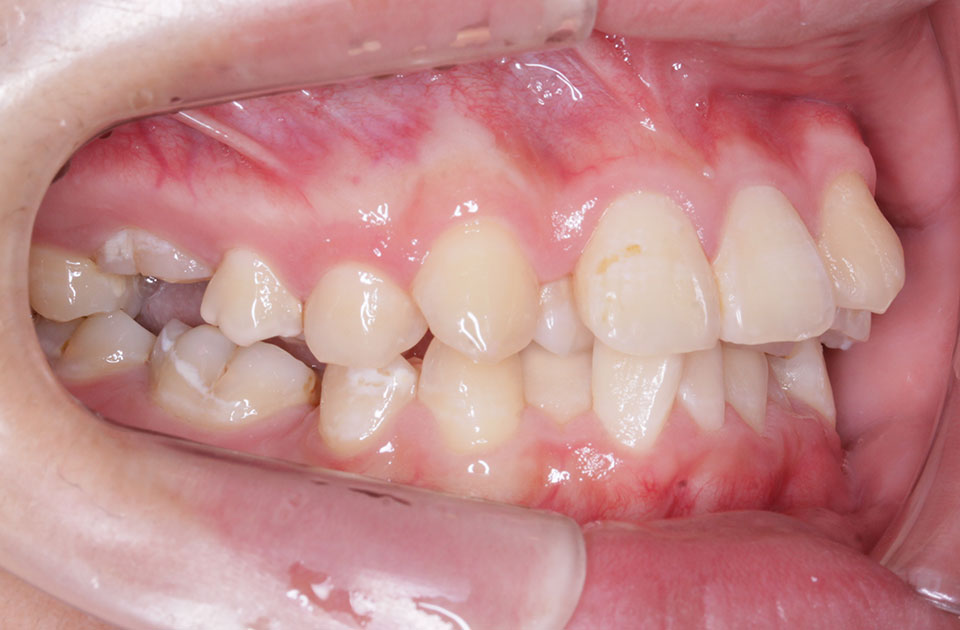

矯正前

矯正前 右側

矯正前 左側